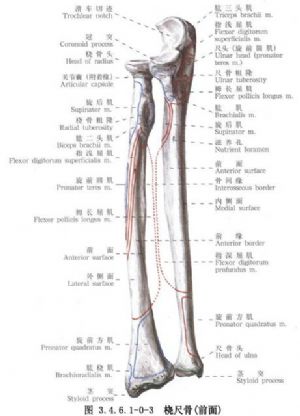

尺桡骨干骨折常见。由于暴力的原因和受伤瞬间肢体的姿式以及肌肉收缩的状态不同,可以发生尺桡骨干双骨折或单骨折。其中,又可发生于不同平面。尺骨干上1/3骨折合并桡骨小头脱位(孟氏骨折Montaggia fracture)。桡骨干下1/3骨折合并下尺桡关节脱位(盖氏骨折Galeazzi fracture)。其中尺桡骨干双骨折占全身骨折的5.41%,为第3位。桡骨骨折占4.23%,为第5位。尺骨骨折占1.05%,为第17位。孟氏骨折占0.63%,为第38位。盖氏骨折占0.35%,为第50位。由于前臂具有旋转功能,一旦发生骨折,除重叠和侧方移位外,尚有严重的旋转移位。因此,对复位的要求较高。如手法复位不满意,难以达到预期功能的恢复,即有手术复位的指征。相关解剖及影像表现见下图(图3.4.6.1-0-1~3.4.6.1-0-6)。